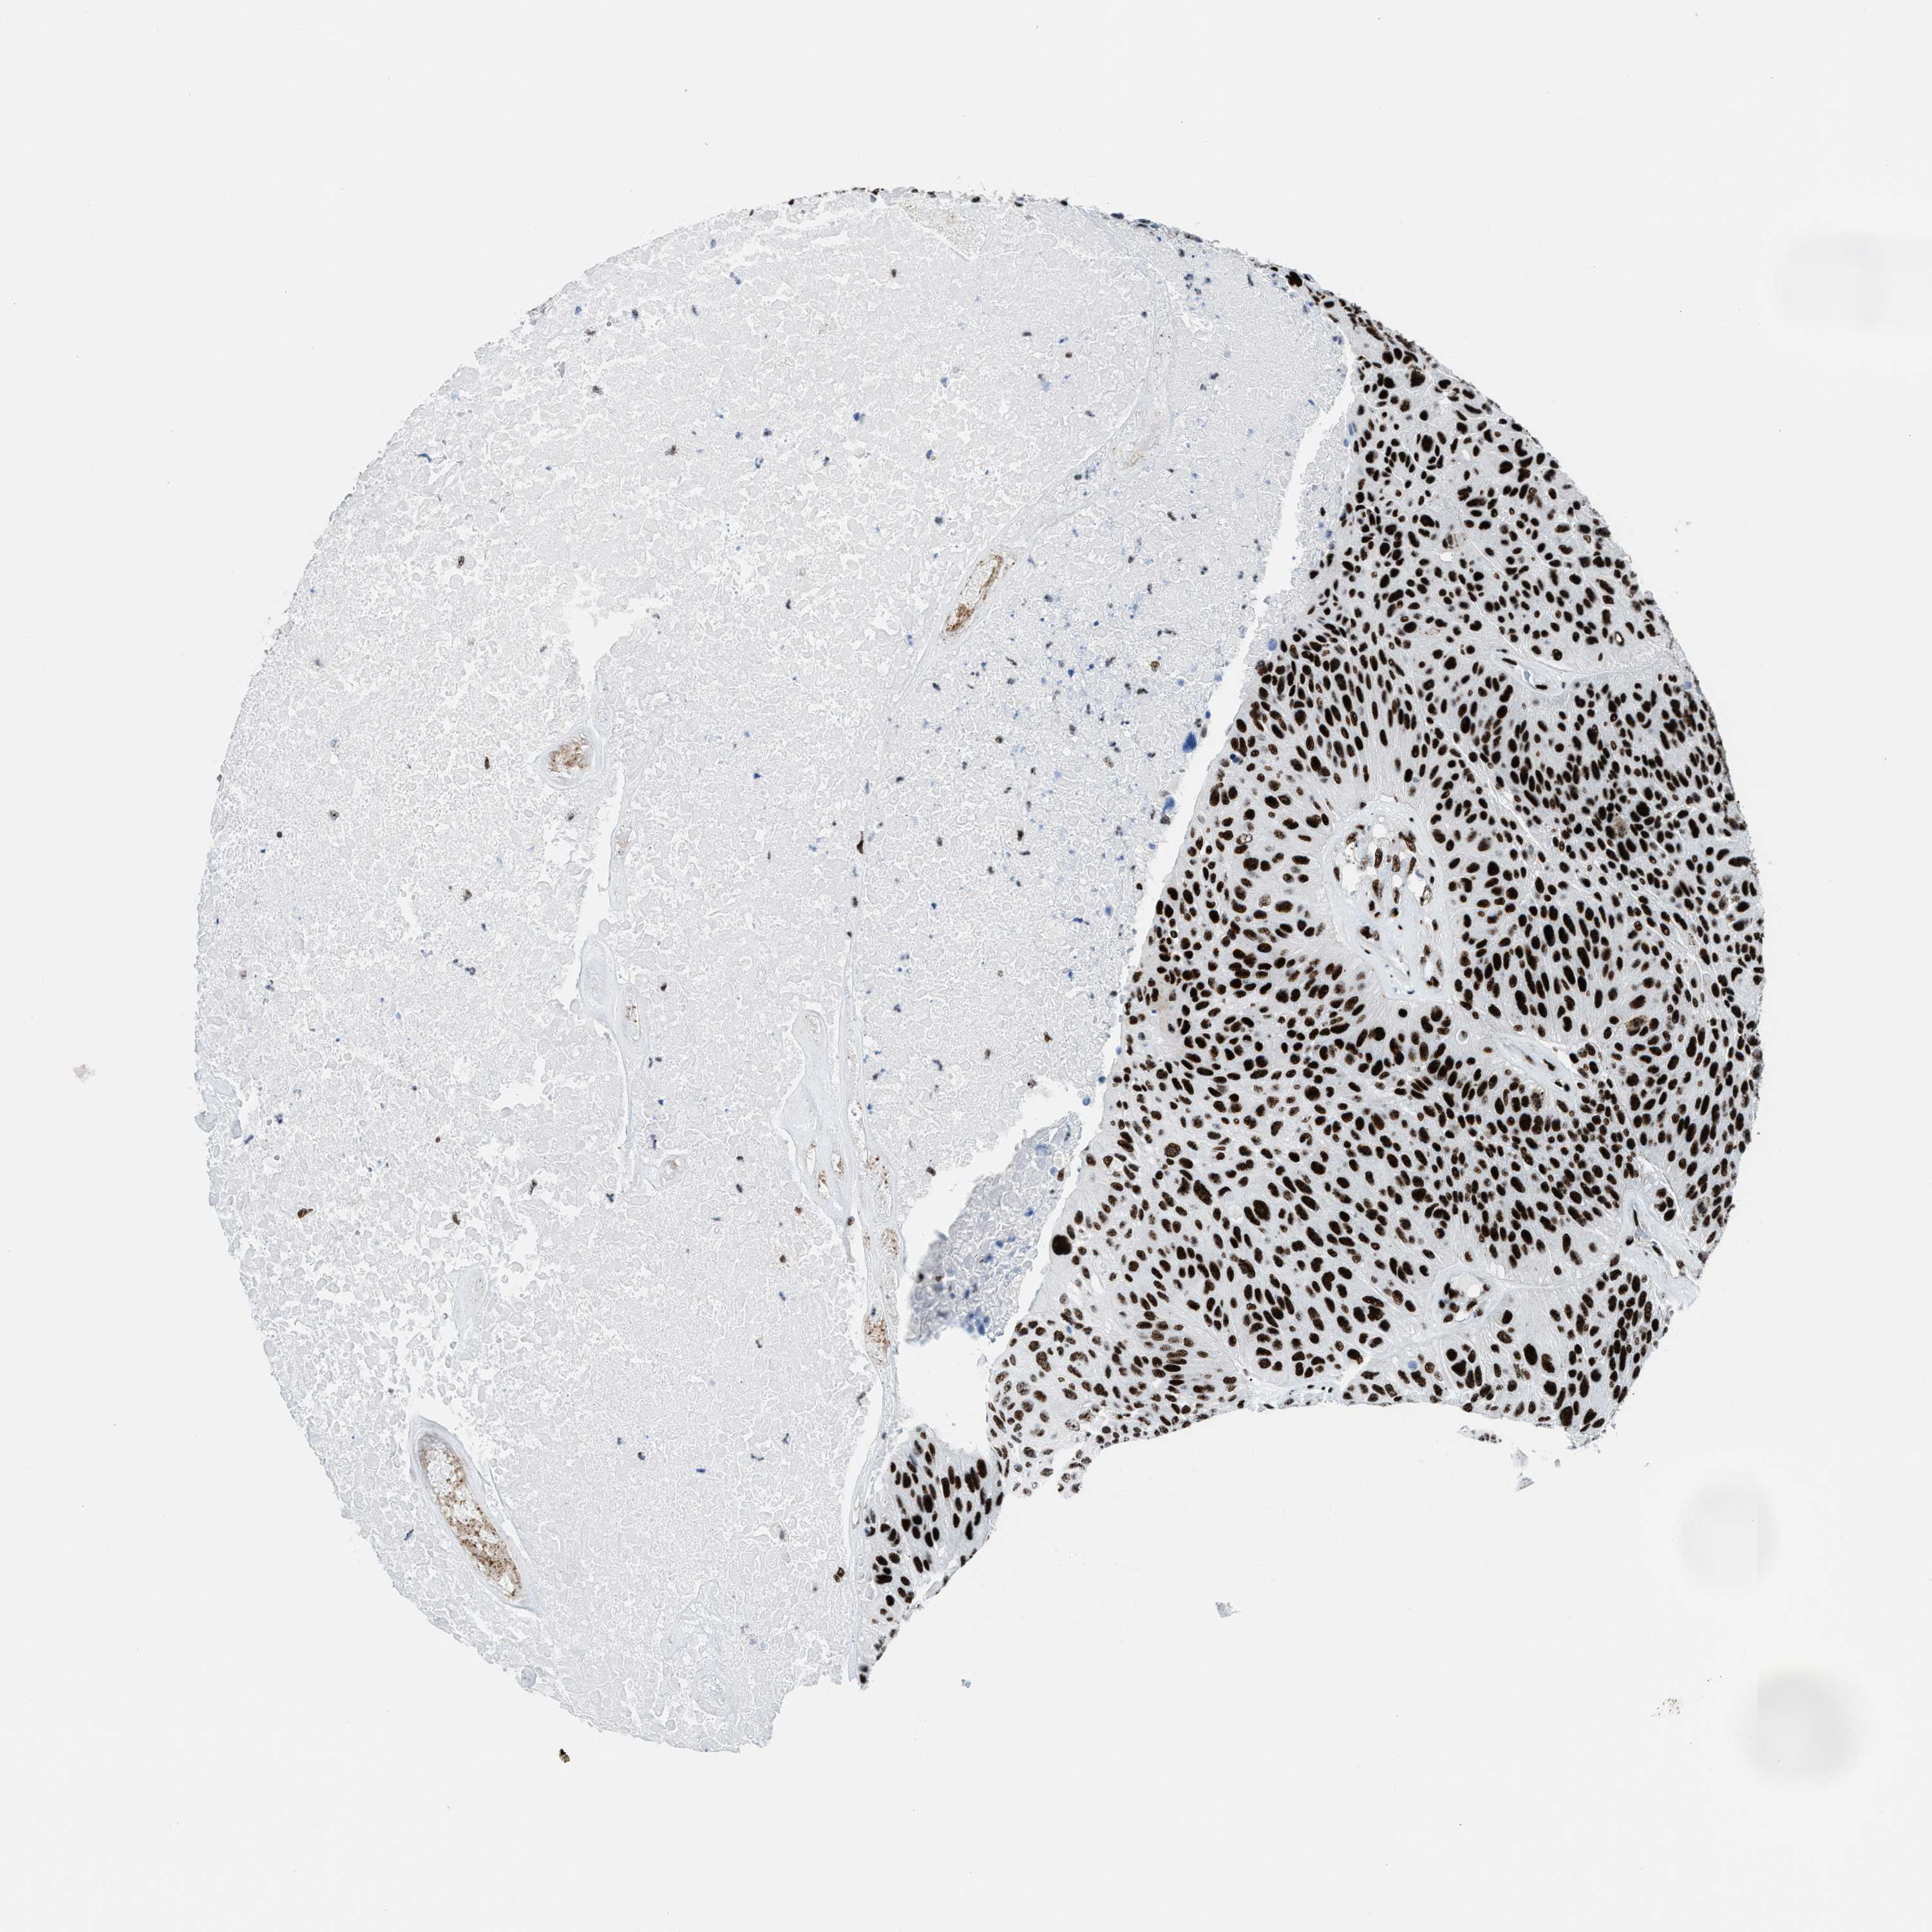

UROTHELIAL CANCER - Protein expressioni

A mouse-over function shows sample information and annotation data. Click on an image to view it in a full screen mode. Samples can be filtered based on level of antibody staining by selecting one or several of the following categories: high, medium, low and not detected. The assay and annotation is described here.

Antibody stainingi

Antibody staining in the annotated cell types in the current human tissue is reported as not detected, low, medium, or high, based on conventional immunohistochemistry profiling in selected tissues. This score is based on the combination of the staining intensity and fraction of stained cells.

Each image is clickable and will lead to virtual microscopy that enables deeper exploration of all samples and also displays staining intensity scores, fraction scores and subcellular localization as well as patient and tissue information for each sample.

Antibody HPA054094

Antibody HPA054559

Antibody CAB022069

Staining

High

Medium

Low

Not detected

Intensity

Strong

Moderate

Weak

Negative

Quantity

>75%

75%-25%

<25%

None

Location

Nuclear

Cytoplasmic/membranous

Cytoplasmic/membranous,nuclear

Urothelial carcinoma, High grade

Urothelial carcinoma, NOS

Urothelial carcinoma, Low grade